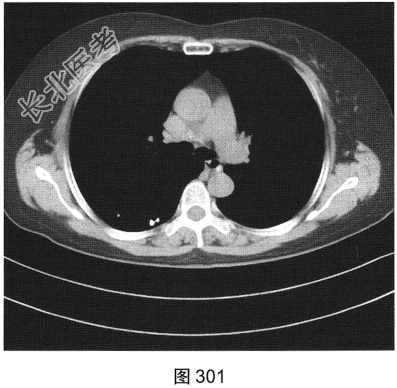

- 多项选择题3.[提示]HRCT图像如图298~图301所示。从患者的HRCT图像中可见哪些阳性征象( )

A、双侧腋窝及纵隔内多发增大淋巴结

B、双肺多发薄壁透亮影

C、小叶间隔增厚

D、右肺多发钙化结节灶

E、双肺多发磨玻璃样密度影

F、支气管扩张

- 多项选择题4.[提示]患者免疫筛查:ANA、RA及干燥综合征相关抗体谱、ACE(一)。根据患者免疫筛查结果, 结合其临床表现和CT影像特征,应优先考虑的诊断是( )

A、肺朗格罕细胞组织细胞增生症

B、支气管扩张

C、淋巴细胞性间质性肺炎

D、肺淋巴管平滑肌瘤病

E、特发性肺间质纤维化

F、肺气肿